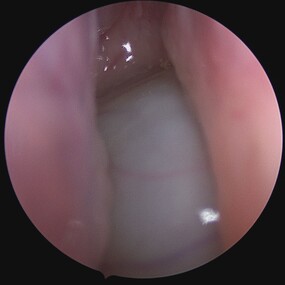

Sinus Pathology

Sino-Nasal Polyps

Sino-Nasal Polyps are non-cancerous growths that develop in the lining of the nose or sinuses. They can obstruct the nasal passages and sinuses, leading to symptoms similar to chronic sinusitis such as nasal congestion, facial pressure, and reduced sense of smell.